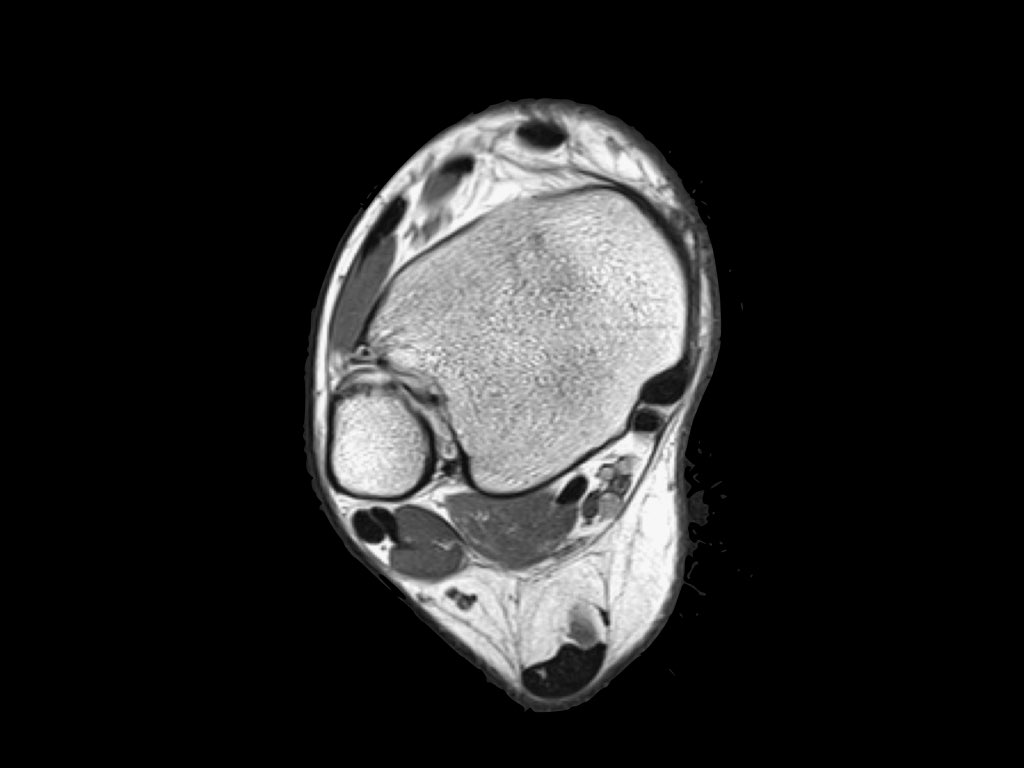

Giải phẫu trên mặt phẳng cắt ngang

Cuộn qua bộ ảnh để xem giải phẫu hệ thống dây chằng trên mặt phẳng cắt ngang.

Bạn có thể nhấp vào ảnh để phóng to.

Các khớp chày mác (syndesmosis) được quan sát rõ nhất trên ảnh cắt ngang:

- Dây chằng chày mác trước (anterior tibiofibular ligament) hay còn gọi là khớp chày mác trước (anterior syndesmosis)

- Dây chằng chày mác sau (posterior tibiofibular ligament) hay còn gọi là khớp chày mác sau (posterior syndesmosis)

- Màng gian cốt (membrana interossei), chạy suốt lên đến chỏm xương mác.